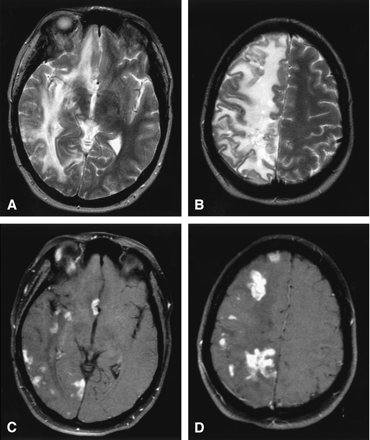

Lymphocytic vasculitis, MR imaging.

A and B, Axial T2-weighted MR images reveal multifocal regions of T2 hyperintensity with surrounding diffuse vasogenic edema limited to the right cerebral hemisphere resulting in mild right to left midline shift.

C and D, Axial T1-weighted postgadolinium MR images with fat saturation depict multifocal enhancing tumefactive lesions, primarily at the subcortical gray-white matter junction and basal ganglia, throughout the right cerebral hemisphere with sparing of the left cerebral hemisphere.